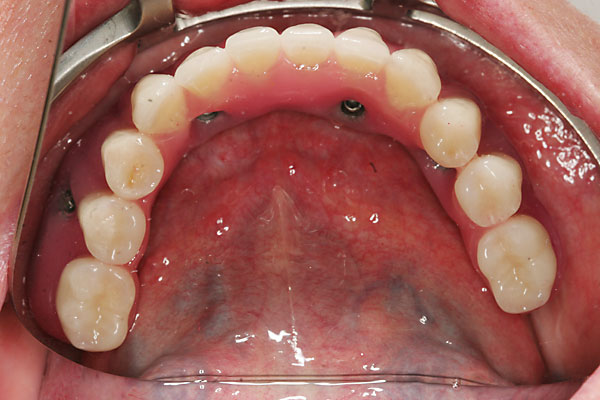

FOTO festsitzende Brücken im Mund |

Fall: festsitzender Zahnersatz im Ober- und Unterkiefer